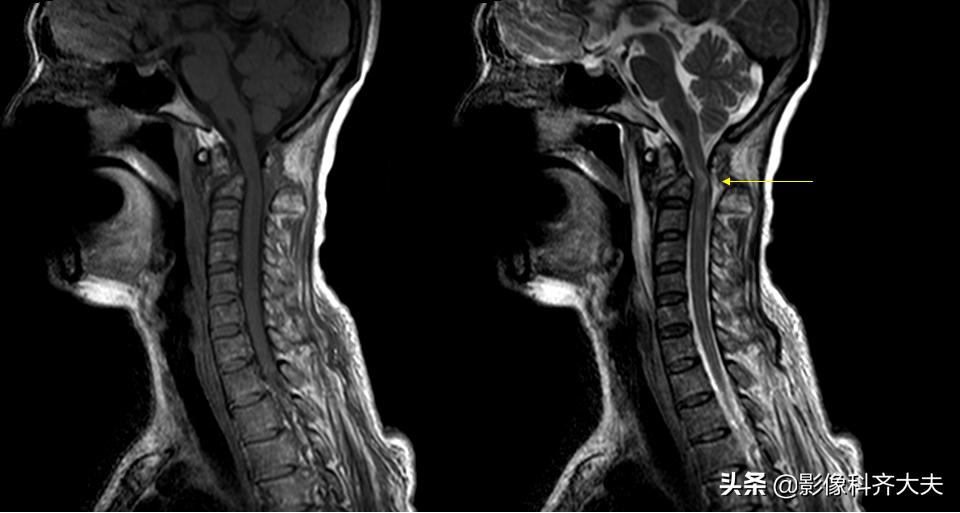

MRI检查

椎体楔状变形

急性期椎体压缩骨折,由于水肿T1WI呈低信号,T2WI信号增高

骨折的椎体压迫脊髓、脊髓水肿、脊髓出血、脊髓断裂及脊髓软化均可显示清楚

椎体压缩骨折可合并前后纵、棘间韧带断裂,可见其连续性中断及信号异常

椎间盘碎裂,表现为形态不规则及T2WI 异常高信号,并可突出压迫脊髓

MRI矢状面枢椎骨折压迫脊髓

颈椎滑脱骨折脊髓挫伤